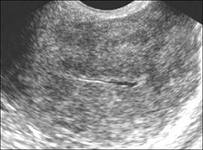

- УЗИ-исследование позволит просмотреть картину, насколько утолщен эндометрий, его контуры и т.д.